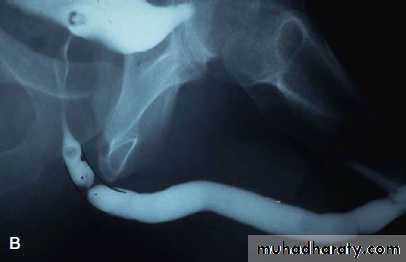

What's This Study & Abnormal Finding

Retrograde urethrography showing stricture of the bulbar part of urethra.